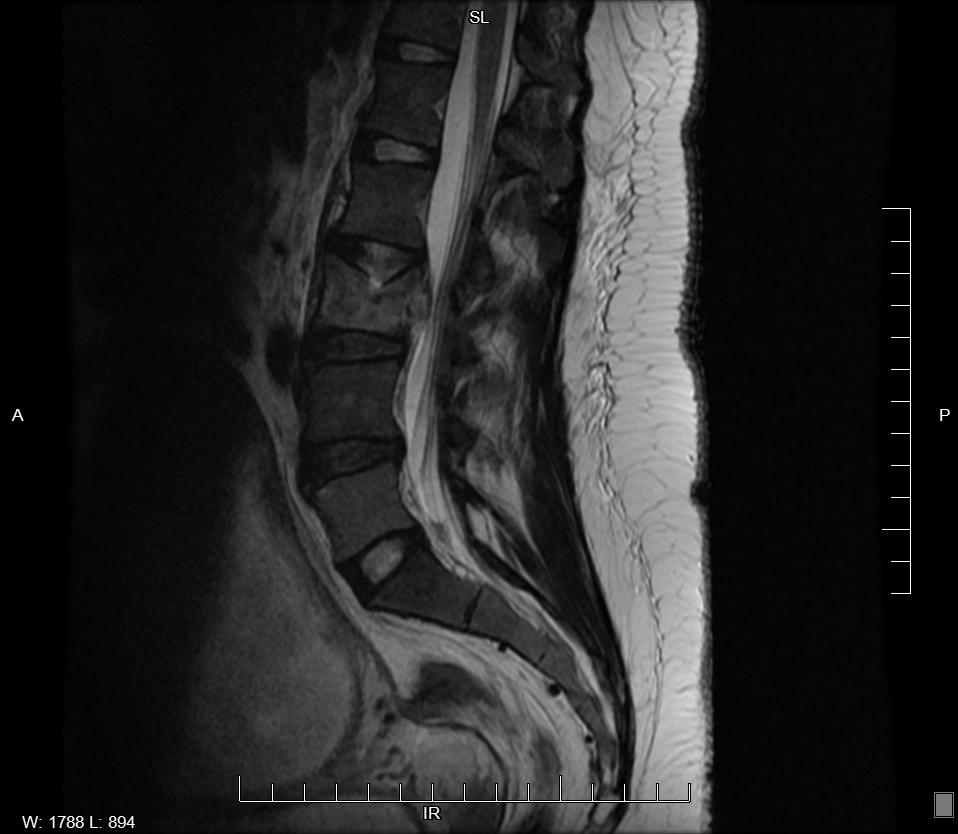

On examination, bruises were noted on bilateral upper and lower limbs. She also had mild tenderness at lower lumbar spine with normal neurological findings. Initial abnormal blood results were platelet 57k/uL and alkaline phosphatase 262u/L. CT Chest showed no evidence of pulmonary embolism or aortic dissection but incidental findings were right lower lobe bronchopneumonia and diffuse osteopenia in thoracic spine with vertebral height loss in T8. Consequent MRI Spine revealed patchy areas of abnormal increased T2 signals consistent with diffuse infiltrative metastasis and pathological compression fracture of L3 and T8. Core bone biopsy of L3 and T8 vertebrae and subsequent bone marrow biopsy reported poorly differentiated adenocarcinoma with associated mucin production and signet ring cell features.